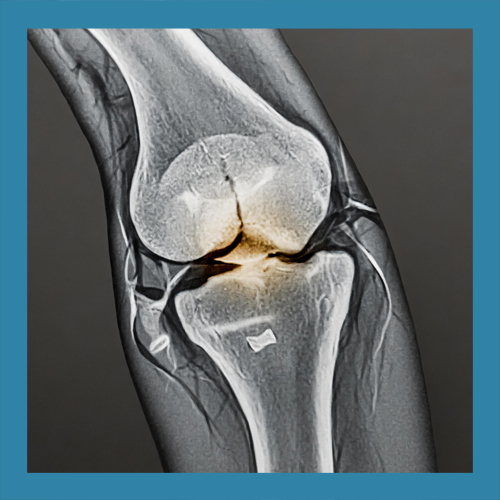

반월상 연골 파열의 치료는 손상의 위치와 정도에 따라 다르게 접근해야 합니다. 경미한 파열은 보존적 치료로 충분히 회복될 수 있지만, 심각한 경우에는 수술이 필요할 수 있습니다. 이를 정확히 판단하기 위해 MRI와 같은 정밀 검사가 필수적입니다.